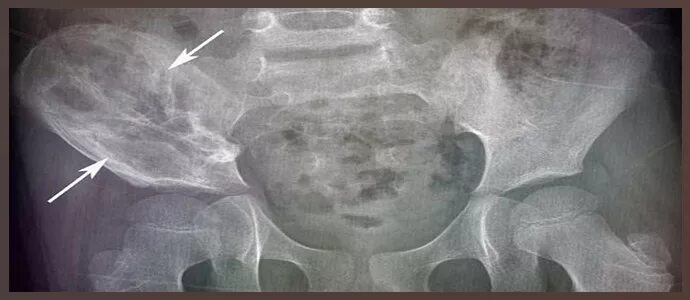

Метастазы в тазобедренном